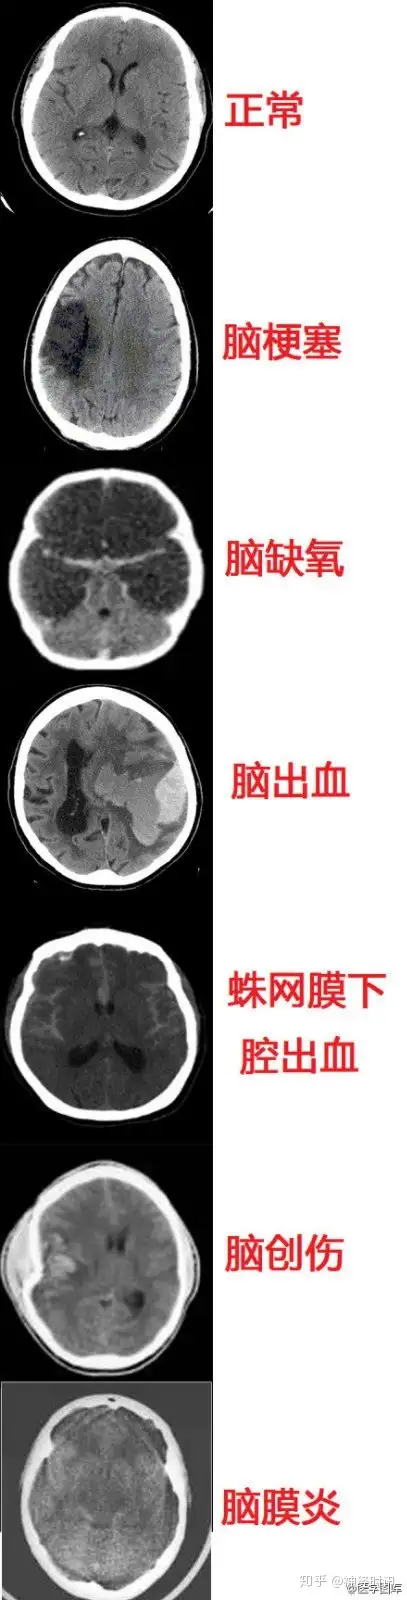

几种常见致死性脑病的CT表现

几种类型脑出血的CT表现